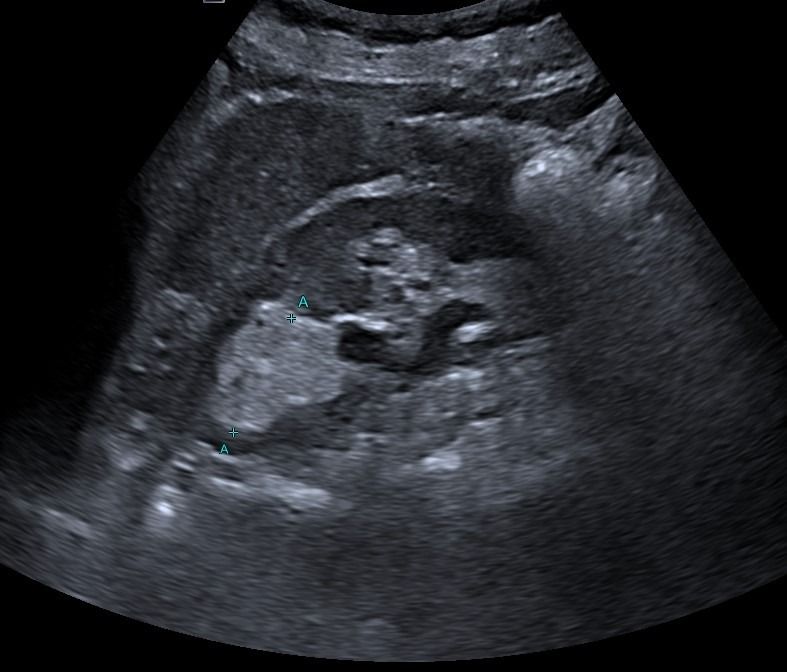

Ποιες τεχνικές χρησιμοποιούνται στην εξέταση του ήπατος;

Με το Τriplex Σπληνοπυλαίου Άξονα αξιολογείται η πυλαία υπέρταση, συνήθως σε έδαφος χρόνιας ηπατοπάθειας και η βατότητα ή θρόμβωση της πυλαίας φλέβας και των ηπατικών φλεβών.

Με την Eλαστογραφία Ήπατος γίνεται αξιολόγηση της ελαστικότητας του ήπατος και υπολογισμός του βαθμού λιπώδους διήθησης ή/και ίνωσης, σε περίπτωση χρόνιας ηπατοπάθειας.